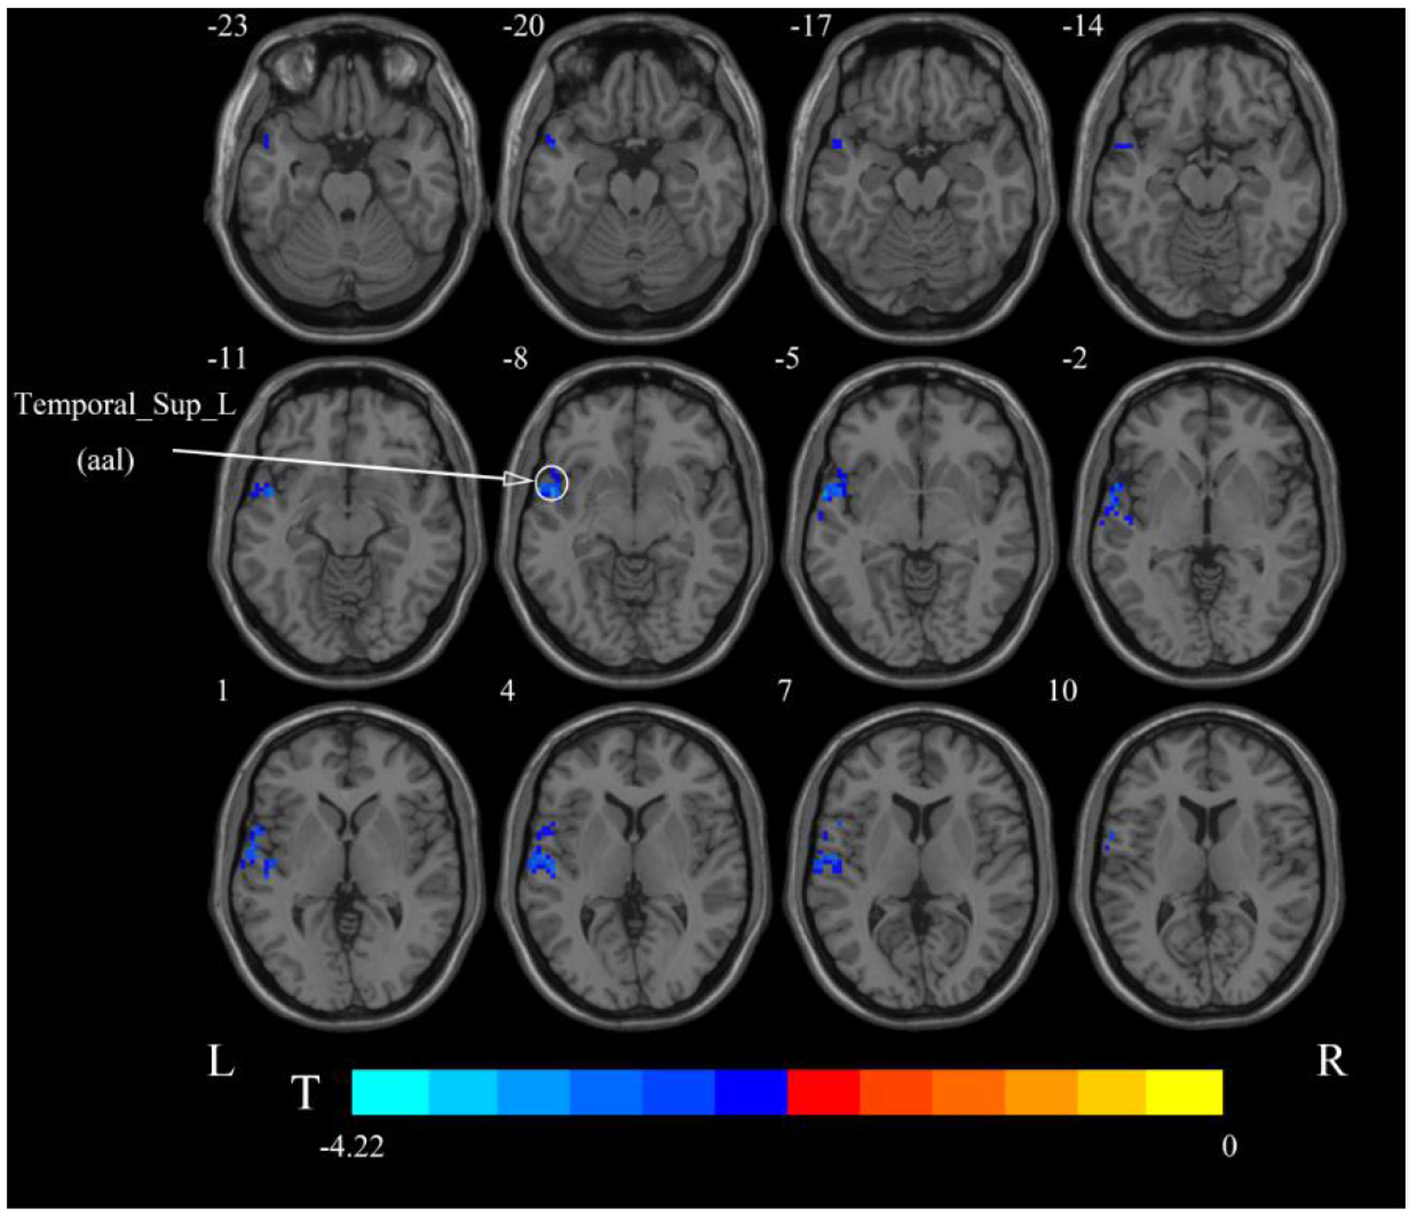

After cerebellar stimulation, in the classical frequency band we found that ALFF was significantly elevated at the pons, right cerebellum, and medulla and significantly reduced at the left temporal lobe (p < 0.05; Figure 3 and Table 1), indicating that unilateral cerebellar stimulation can produce increased spontaneous neural activity in the cerebellum and brainstem and suppress activity at the contralateral temporal lobe. In addition, we found that ALFF at the left temporal lobe was also decreased in the slow-4 band and slow-5 band (p < 0.05; Figures 4, 5 and Table 1).

Figure 3. Statistical maps showing ALFF change pre- and post-rTMS in the classical frequency band. Warm colors showing ALFF increased and cool colors showing ALFF decreased after rTMS p < 0.05.

Figure 4. Statistical maps showing ALFF change pre- and post-rTMS in the slow-4 band. Cool colors showing ALFF decreased after rTMS p < 0.05.

Figure 5. Statistical maps showing ALFF change pre- and post-rTMS in the slow-5 band. Cool colors showing ALFF decreased after rTMS p < 0.05.

In addition, we also found decreased ALFF in the contralateral temporal lobe after cerebellar rTMS, suggesting a possible inhibitory effect of cerebellar rTMS on the contralateral temporal lobe. Previous studies have shown that swallowing is governed by multiple parts of the cerebral cortex, such as the sensory/motor cortex, prefrontal areas, anterior cingulate, insula, parietal and temporal lobes (Hamdy et al., 1999; Martin et al., 2001; Suzuki et al., 2003; Babaei et al., 2012, 2013; Ushioda et al., 2012). The temporal lobe is thought to be involved in taste recognition during swallowing (Small et al., 1999). Since the swallowing action directly induced by cerebellar rTMS skips taste recognition, the temporary lobe suppression may be related to the negative feedback between cerebellum and temporal lobe. The cortical ALFF results showed an inhibitory effect of cerebellar rTMS on the contralateral temporal lobe in both the slow-4 and slow-5 frequency bands. However, unlike the classical band, no functional changes in the pons, medulla oblongata, or cerebellum were found in either frequency band. This suggests that the activity of these regions may be manifested in the entire classical frequency band rather than in some part of it.